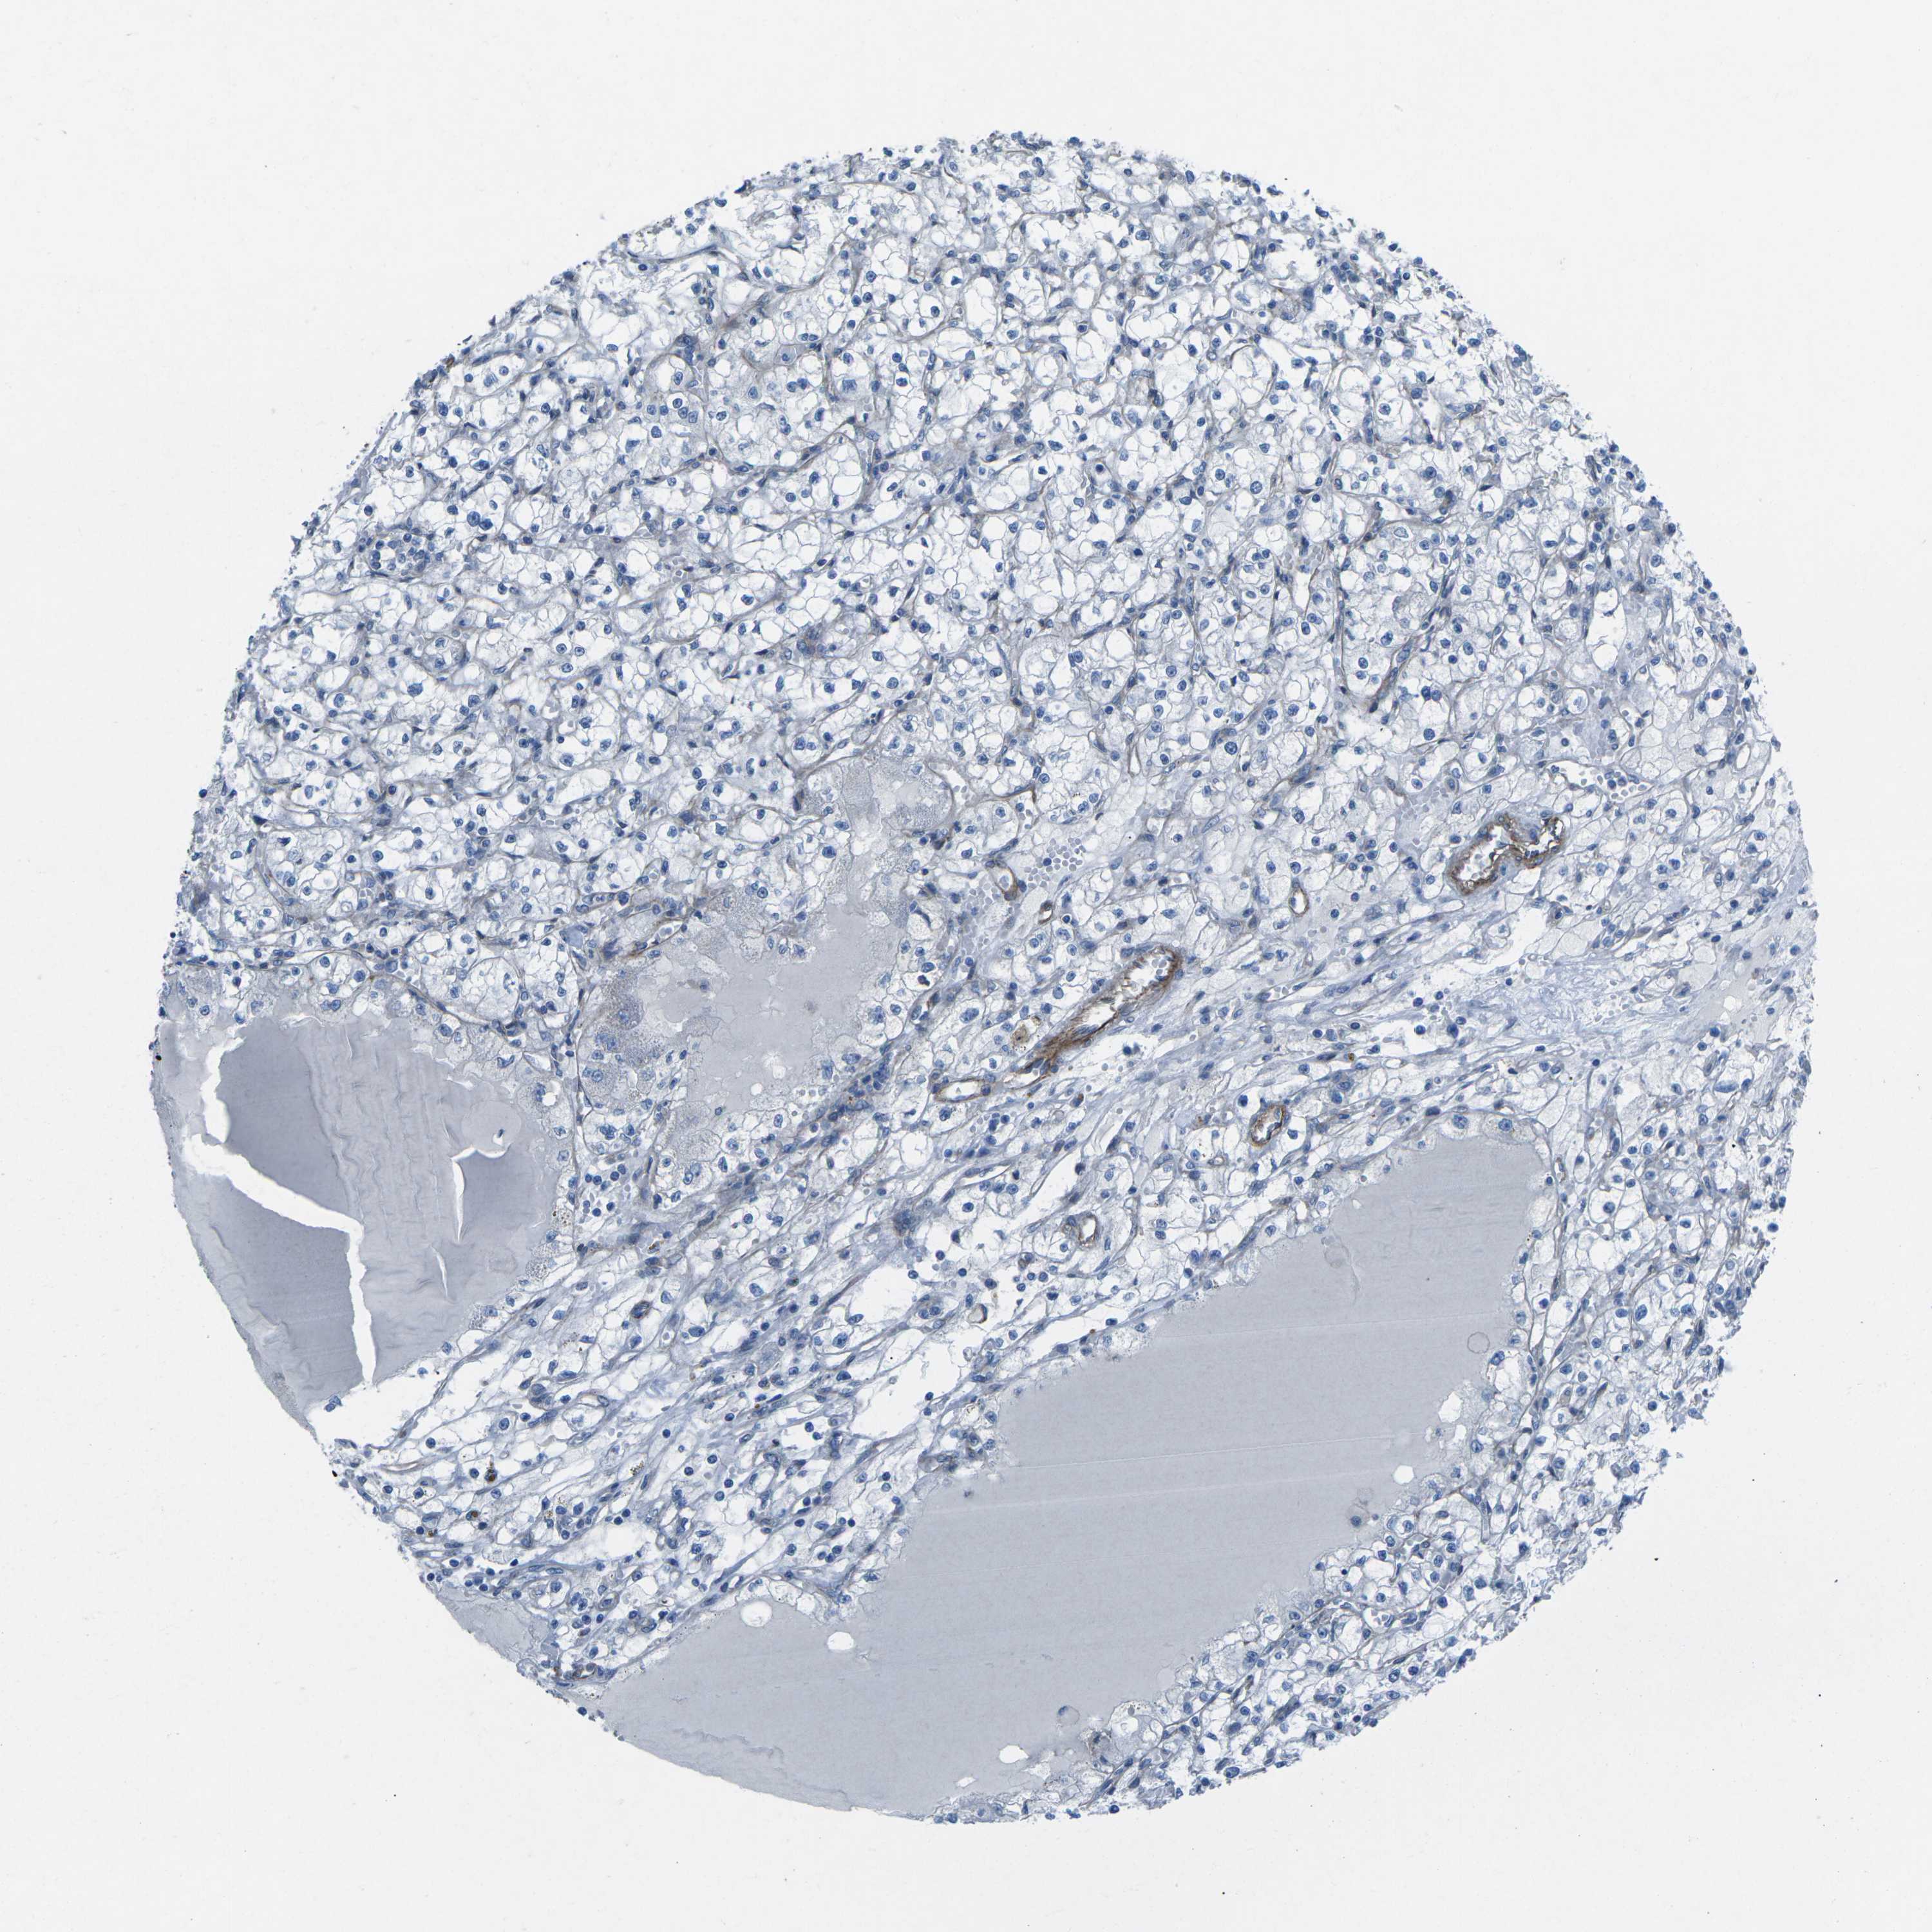

KIDNEY RENAL CLEAR CELL CARCINOMA (VALIDATION) - Interactive survival scatter ploti

The Survival Scatter plot shows the clinical status (i.e. dead or alive) for all individuals in the patient cohort, based on the same data that underlies the corresponding Kaplan-Meier plots. Patients that are alive at last time for follow-up are shown in blue and patients who have died during the study are shown in red.

The x-axis shows the expression levels (FPKM) of the investigated gene in the tumor tissue at the time of diagnosis. The y-axis shows the follow-up time after diagnosis (years). Both axes are complimented with kernel density curves demonstrating the data density over the axes. The top density plot shows the expression levels (FPKM) distribution among dead (red) and alive patients (blue). The right density plot shows the data density of the survived years of dead patients with high and low expression levels respectively, stratified using the cutoff indicated by the vertical dashed line through the Survival Scatter plot. This cutoff is automatically defined based on the FPKM cutoff that minimizes the p-score. The cutoff can be changed by dragging the vertical line or by entering a cutoff value in the square labeled "Current cut-off".

Under the Survival Scatter plot the p-score landscape (black curve; left axis) is shown together with dead median separation (red curve; right axis). Dead median separation is the difference in median mRNA expression between patients who have died with high and low expression, respectively. It is calculated as follows: median FPKM expression of dead patients with high expression - median FPKM expression of dead patients with low expression. This is intended to aid the user in visually exploring custom cutoffs and the associated p-scores and dead median separation.

Individual patient data is displayed and can be filtered by clicking on one or more of the category buttons on the top of the page. Categories describing expression level and patient information include: high, low, alive, dead, female, male and tumor stages. The scale of the x-axis can be toggled between linear and log-scale by clicking on the "x log" button. Mouse-over function shows TCGA ID, patient information and mRNA expression (FPKM) for each patient.

& Survival analysisi

Kaplan-Meier plots summarize results from analysis of correlation between mRNA expression level and patient survival. Patients were divided based on level of expression into one of the two groups "low" (under cut off) or "high" (over cut off). X-axis shows time for survival (years) and y-axis shows the probability of survival, where 1.0 corresponds to 100 percent.

UTRN is validated prognostic, high expression is favorable in Kidney Renal Clear Cell Carcinoma (validation)

: 47.69

Average pTPM 53.2

Number of samples 100